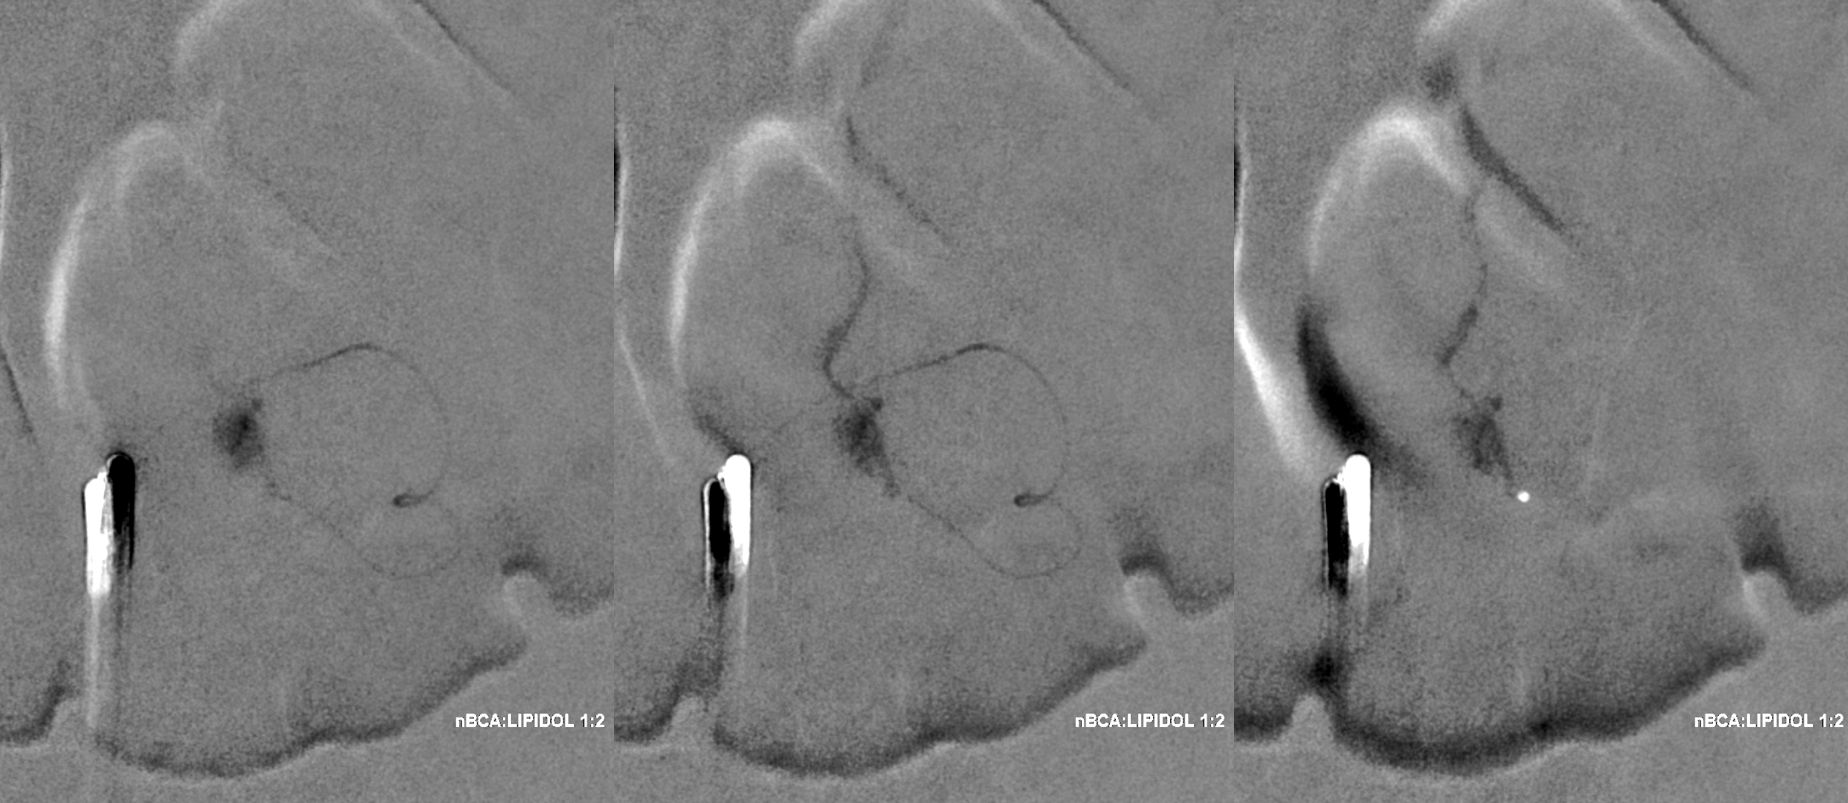

A 1:2 nBCA:lipidol dilution was chosen because of additional arterial inflows over which we had limited control (we usually use 1:1). Result seems good

Not so fast. Fistula still alive — which is exceptionally rare after putting this much glue into the vein. Yes, glue is diluted but still its plenty. There is also heparin on board — we pre-treated given massive venous congestion and concern for thrombosis. Still, this is extremely rare. Much slower, but still alive. It is a mistake to hope it thromboses later. Very likely it will not, and hoping it will only contributes to the reputation that endovascular is less effective than surgery.

Re-catheterization (left and center) and additional nBCA injection — even more dilute now that the vein outflow is relatively protected. We think this is good now.